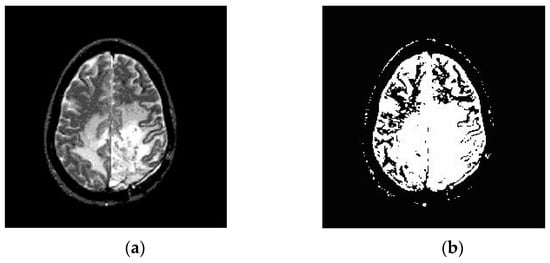

3.2. Segmentation

3.2.1. Otsu’s Threshold